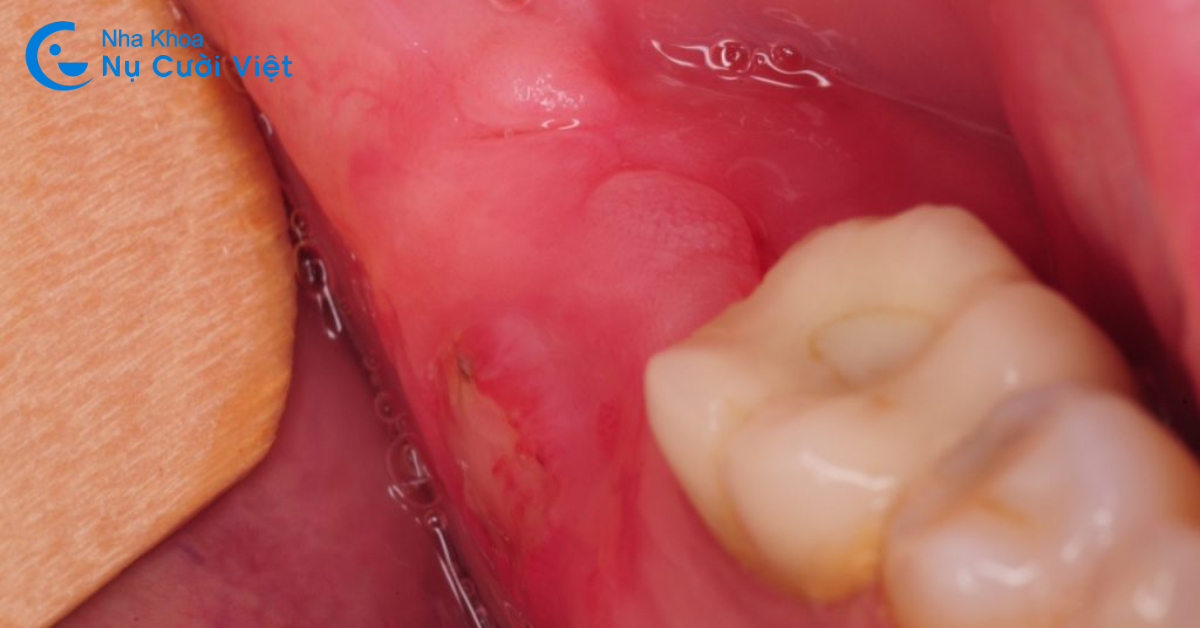

Triệu chứng mọc răng khôn cũng khá phổ biến trong quá trình mọc răng khôn chính là sưng lợi. Kích thước của răng khôn khá to mà cung hàm chúng ta đã trở nên hẹp dần. Răng khôn khi mọc không đủ vị trí để mọc sẽ mọc lệch, mọc ngầm. Răng không dễ dàng trồi lên trên bề mặt được. Dẫn đến hiện tượng nướu (lợi) sưng đỏ. Kéo theo việc này sẽ là đau nhức kéo dài và trầm trọng hơn nếu không được xử lí.

Việc sưng lợi khi mọc răng khôn ngoài việc đau nhức còn gây nên những bất tiện khác. Tiêu biểu là cản trở việc ăn nhai, dễ cắn vào má khi ăn uống hoặc nói chuyện.